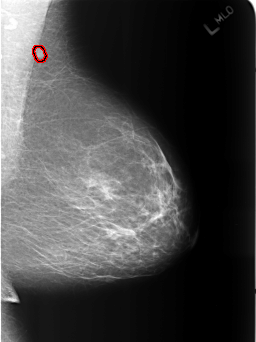

B_3186_1.LEFT_MLO

LEFT_MLO LINES 5464 PIXELS_PER_LINE 4096 BITS_PER_PIXEL 12 RESOLUTION 50 OVERLAY

FILE: B_3186_1.LEFT_MLO.OVERLAY

TOTAL_ABNORMALITIES 1

ABNORMALITY 1

LESION_TYPE MASS SHAPE OVAL-LYMPH_NODE MARGINS CIRCUMSCRIBED

ASSESSMENT 2

SUBTLETY 4

PATHOLOGY BENIGN_WITHOUT_CALLBACK

TOTAL_OUTLINES 1

BOUNDARY